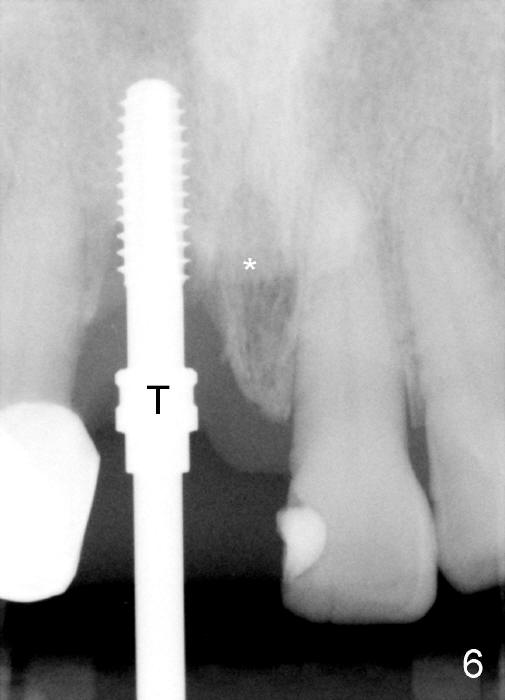

A 64-year-old lady requests replacing #7 and 8 crowns (Fig.1,2). When #8 is extracted, the labial plate is found to be missing (Fig.3). Following 2 mm pilot drill (Fig.4,5 P), 3.8 mm tap drill (Fig.6,7 T) and 4.5x14 mm implant (Fig.8 I) and 4.8 mm abutment (Fig.9 A), corticocancellous bone is harvested from the left tuberosity and placed in the labial gap of the socket (Fig.10 G). Collagen dressing is placed over the bone graft (Fig.11 C). The former is secured in place by an immediate provisional (P).